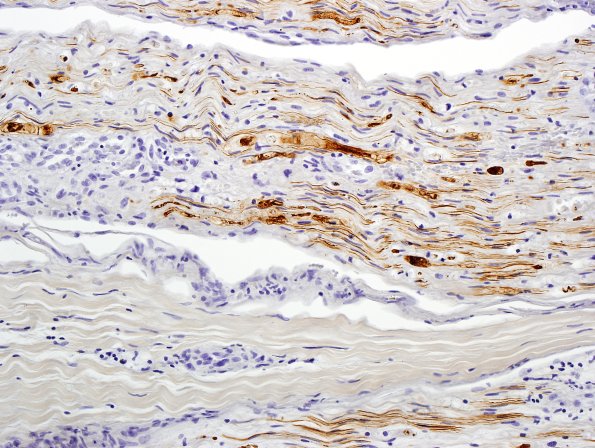

Washington University Experience | PERIPHERAL NEUROPATHY | 11 VASCULITIS - VASCULOPATHY | 3 Vasculitis - NOS | 4B3-Vasculitis-Case-4B-NF-6.jpg

4B3-5 Higher magnification images show fragments of intact axons and clumps of degrading neurofilaments, often within Schwann cells as “ovoids” (a teased fiber term) and possibly within macrophages. (NF IHC)